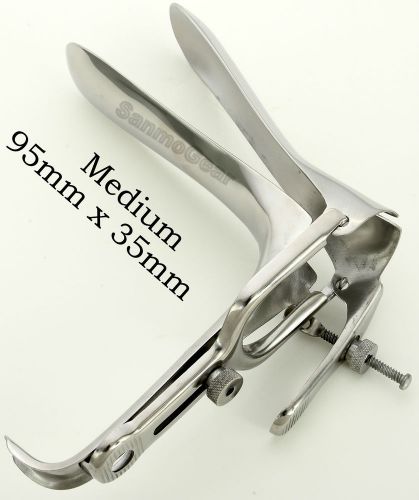

Grave Vaginal Speculum "Medium" Gynecology Surgical Instrument